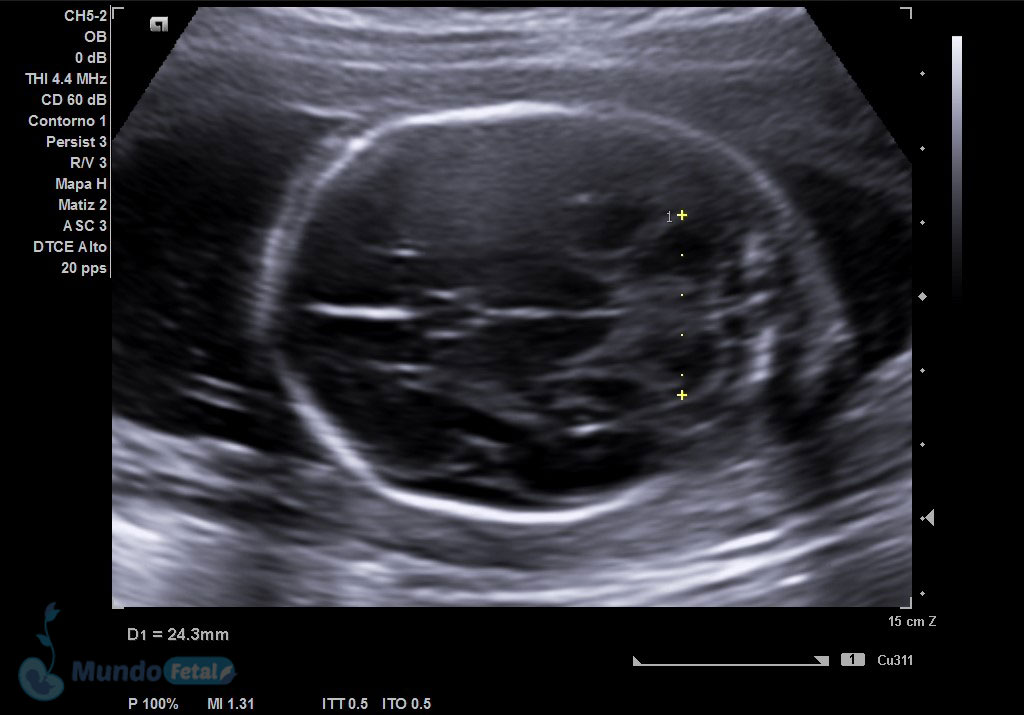

Ultrasonido 2do Trimestre 18-23 Semanas (Estructural o Anatómico)

Entre las 18 y 22 semanas, el feto ha desarrollado la mayoría de sus estructuras anatómicas, permitiéndonos valorar de manera detallada todos los órganos del bebe, descartando anomalías anatómicas fetales y datos de cromosomopatías. Prediciendo además preeclampsia (Doppler de arterias uterinas) y parto prematuro (por medio de la medición de la longitud del cérvix). En manos expertas, la detección de anomalías anatómicas supera el 80%.

ANATOMICO-ORBITAS